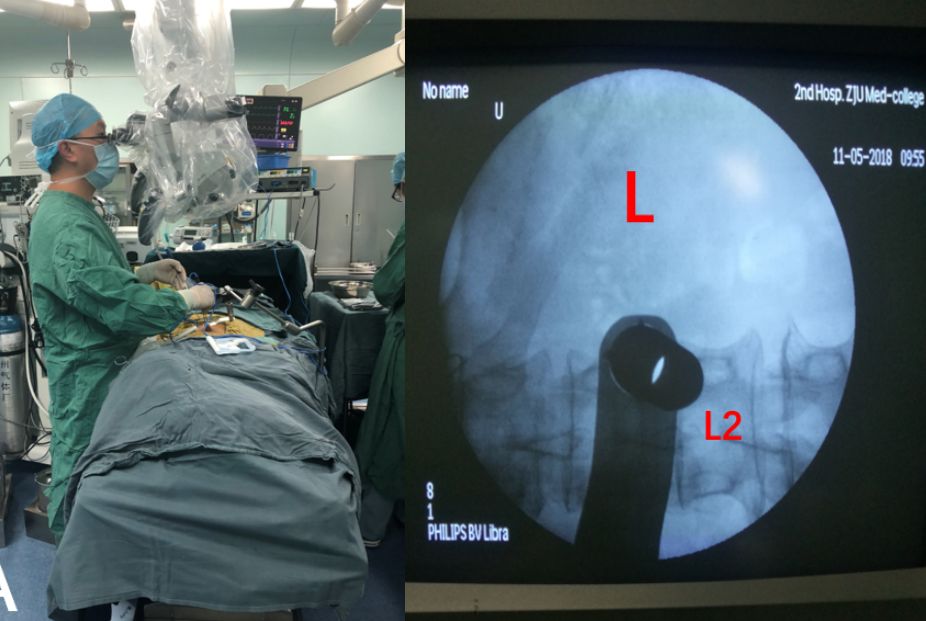

经科室讨论,明确有手术指证。于2018-05-11全麻下行经皮套筒腰1/2椎管内病损切除术。

手术经过及镜下所见(图2,3):取俯卧位,以L1-2为中心中线左侧旁开2.5cm取约2cm直切口,切开皮肤及肌肉筋膜,经最长肌和多裂肌间隙应用扩张器逐级扩张撑开椎旁肌肉,置入工作套筒至L1-2左侧椎板间,C臂机定位无误,支架固定,显微镜下暴露左侧L1/2椎板间隙,磨钻磨除L1左侧下半椎板,咬除黄韧带后见脊膜,切开硬脊膜及蛛网膜,显露肿瘤,呈囊性变,约2.5cm*1.5cm*1.5cm大小,色灰红,边界清,血供一般,电凝肿瘤后切开肿瘤包膜,瘤内减压后,将肿瘤拖出硬膜外,见一神经根穿过肿瘤,予电凝后离断上下极,全切肿瘤,7-0prolene线缝合硬脊膜,逐层缝合肌肉及筋膜,皮内缝合皮肤。术中出血5ml左右。

图2. 手术经过: A.经皮套筒显微外科手术;B.术中C臂机定位;C.套筒置入支架固定;D.术后切口,长度不到2cm。